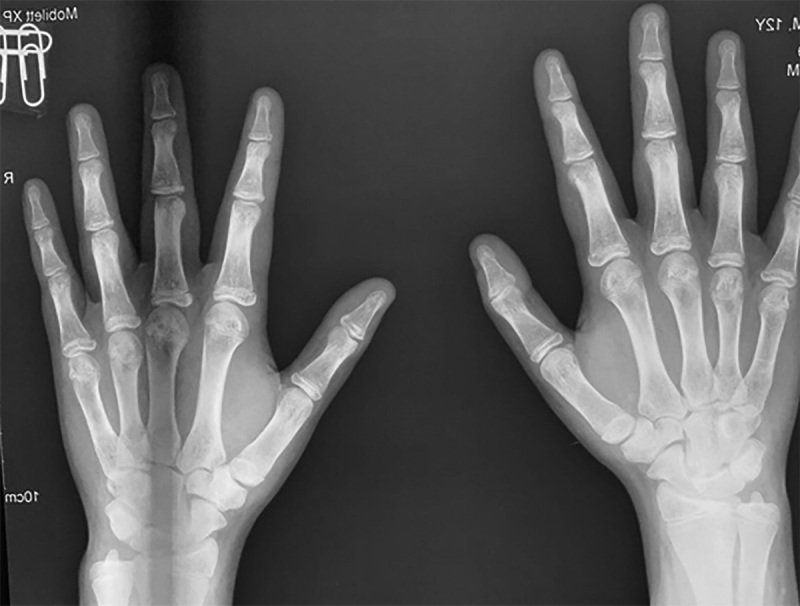

This article describes the first experience of successful use of growth hormone (GH) in combination with an aromatase inhibitor (AI), in a 14-year-old boy. At the age of 7, he presented with headaches, nausea and vomiting, and MRI revealed a craniopharyngioma (CP). An Ommaya system was implanted, and radiation therapy was performed. As a result of treatment, GH deficiency and secondary hypothyroidism developed. At age 9 years, signs of puberty appeared. Growth rate remained satisfactory until the age of 14 years. At the age of 14 growth rate slowed down, which was the reason for appointment. Upon examination, the bone age was 16 years and the projected final height without therapy was 162 cm. Given the poor growth prognosis, IA anastrozole in combination with GH was prescribed. During two years of therapy the growth gain amounted to 12.5 cm. This observation demonstrates that normal growth rates in patients with CP do not indicate preserved somatotropic function of the pituitary gland. With preserved sexual function, early or premature puberty may be observed. In such cases, IA can be prescribed in addition to GH - these are medications that inhibit the closure of growth. GH therapy in combination with IA is highly effective and safe in patients with GH deficiency after treatment of KF during puberty and allows to achieve good growth parameters.